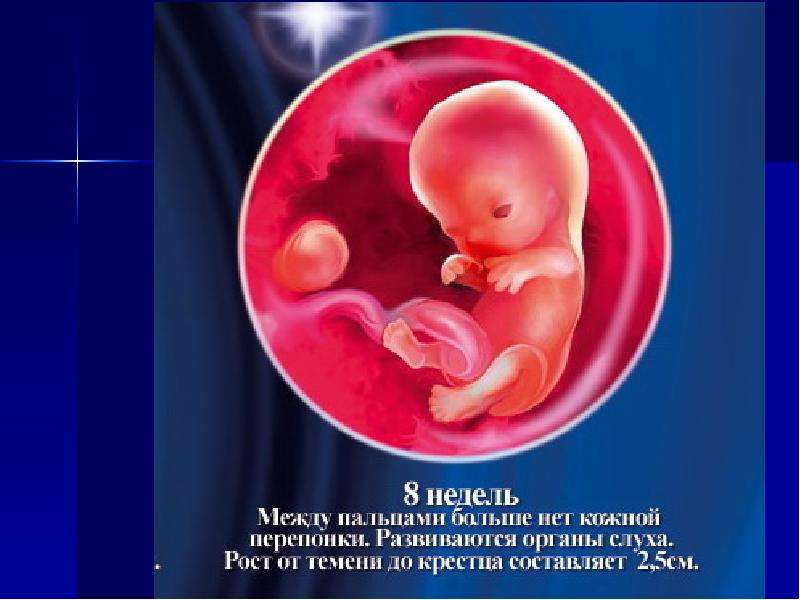

Удивительные фотографии эмбриона на 8 неделе беременности